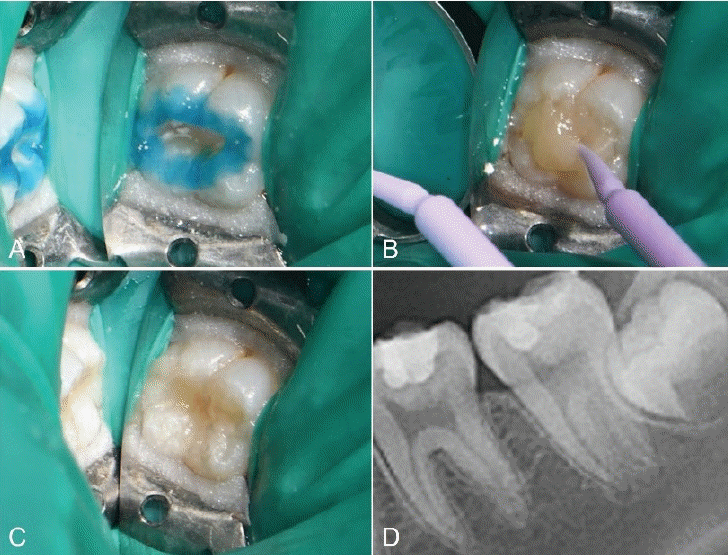

Fig. 1.

Initial examination radiograph and clinical photograph. A. No loss of tooth structure is observed. B. Pre-operative radiograph. C. Caries of dentin is seen on olwer left second molar.

Fig. 2.

A. Caries excavation and cavity preparation is done. B. Base restoration with glass ionomer is done. C. Stamp is obtained using flowable resin and microbrush. D. Photograph after applying stamp on teeth. E. Postoperative periapical radiograph